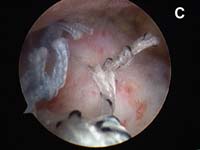

For the most common type of rotator cuff tears, the tendon of the rotator cuff muscle called the supraspinatus will have torn and pulled back slightly from its normal attachment at the greater tuberosity atop the humerus. These smaller tears which are "non-retracted" or "minimally-retracted" only need to be freshened or débrided back to stable, healthy tendon tissue, then mobilized back to the tuberosity and fixed in place. (See Fig. 9) When using an all arthroscopic technique, the surgeon will employ special devices called "suture anchors" to hold the tear in position when it heals. These "anchors" can be made of metal or absorbable compounds. They are screwed or pressed into the bone of the attachment site and the attached sutures are used to tie the edge of the rotator cuff in place.

As tears become larger, they deform and the tendon tissue "shrinks". Thus, larger tears need to be refashioned, repaired side-to-side, or "zipped" closed using a technique called margin convergence. This technique is analogous to zippering shut an open tent flap. The rotator cuff tissue is freed from a scarred, retracted position and repaired side-to-side to ‘close the tent flap’ and restore the tissue over the top of the humeral head. (See Fig.4 and Fig.10) The repaired cuff tissue is then fixed to the site it originally tore away from using specially-designed implants called suture anchors. These are metallic or absorbable plastic devices that secure sutures to the bony attachment. The sutures are then sewn through the torn edge of the cuff to complete the repair.

- The tear must be fixed into place using specially-designed suture anchors that allow the surgeon to approximate the cuff tear securely to the bone.